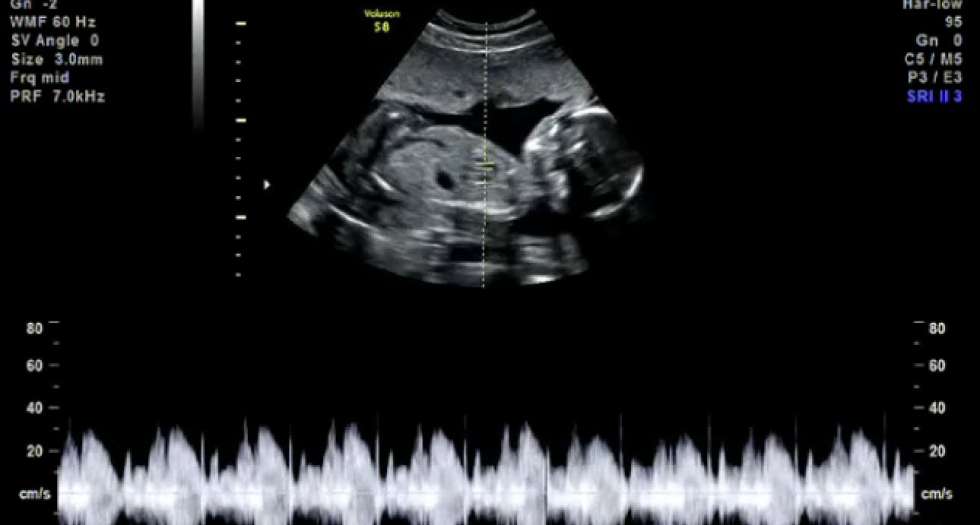

به همین دلیل، تشخیص جنسیت جنین با گوشسنجی صدای قلب ممکن نیست و برای تشخیص جنسیت جنین از روشهای دیگر مانند سونوگرافی استفاده میشود. در سونوگرافی، تصویری از جنین به نمایش در میآید که جنسیت آن توسط پزشک مشخص میشود.

سونوگرافی رشد جنین در چند هفتگی است ؟

سونوگرافی رشد جنین در طول دوران بارداری ممکن است در موارد مختلف صورت بگیرد. در این رابطه، سونوگرافی برای اندازهگیری رشد جنین و بررسی سلامت آن در طول بارداری انجام میشود و معمولاً در موارد زیر در نظر گرفته میشود:

- برای بررسی تایید بارداری و تشخیص مکان جنین، سونوگرافی در هفتههای اولیه بارداری (حدوداً ۶-۸ هفته) انجام میشود.

- برای بررسی رشد و توسعه جنین و سلامت آن، سونوگرافی در هفتههای بعدی بارداری (حدوداً ۱۸-۲۲ هفته) نیز انجام میشود. در این مرحله، سونوگرافی میتواند کمک کند تا سایز جنین، وزن، سلامت قلب، اندازه سر و شکم، طول استخوانها و غیره بررسی شوند.

- در برخی موارد خاص مانند وجود مشکلاتی در بارداری، سابقهی قبلی بارداری ناکامی، یا در صورت نیاز به بررسیهای بیشتر، سونوگرافی در هفتههای بیشتری نیز انجام میشود.

در هر صورت، زمان دقیق برای انجام سونوگرافی برای رشد جنین بستگی به شرایط هر بارداری و توصیههای پزشک خود دارد. معمولاً پزشکان برای بررسی رشد جنین و سلامت آن، سونوگرافیهای مکرری در طول دوران بارداری تجویز میکنند.

برای بررسی رشد جنین در هر هفته بارداری، میتوان از سونوگرافی استفاده کرد. سونوگرافی یکی از مهمترین و دقیقترین روشهای بررسی رشد جنین و سلامت آن در طول دوران بارداری است.

در سونوگرافی، با استفاده از امواج صوتی، تصاویری از جنین، رحم، پلاکنتا و رگهای خونی مادر ساخته میشود. در هر سونوگرافی، پزشک میتواند اندازه جنین، وزن، سلامت قلب، اندازه سر و شکم، طول استخوانها و غیره را بررسی کند. بر اساس این اطلاعات، میتوان به رشد جنین و سلامت آن پی برد.

معمولاً پزشکان برای بررسی رشد جنین و سلامت آن، سونوگرافیهای مکرری در طول دوران بارداری تجویز میکنند. با استفاده از این روش، میتوان نشان داد که جنین در هر هفته بارداری چه میزان رشد کرده است و آیا رشد آن نسبت به میانگین رشد جنینهای در همان هفته بارداری، به خوبی است یا خیر.